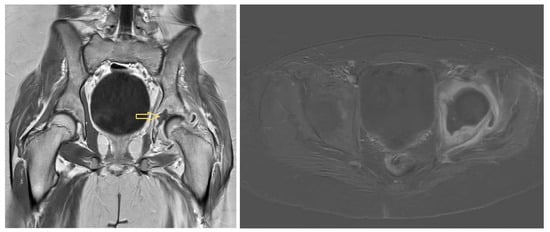

3.1.1. Patient 1

3.1.2. Patient 2

3.1.3. Patient 3